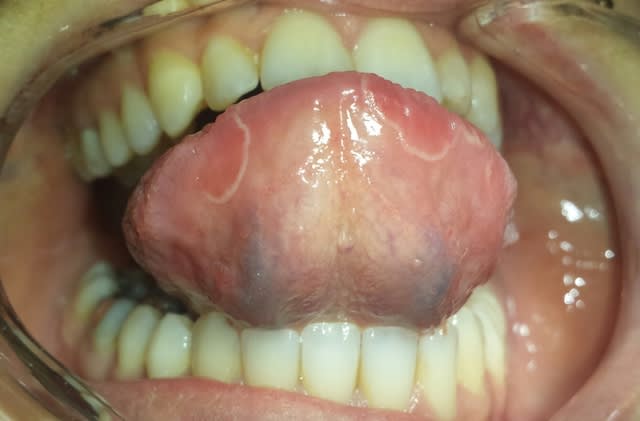

Bonjour, je vous présente le cas d'une patiente du jour:

Patiente de 27 ans, pas de problème de santé, pas de médicament, pas de tabac, présente depuis hier une lésion au niveau de la langue. Ne se décolle pas au grattage, léger picotement ressenti.

Langue géographique

Langue géographique oui et macroglossie j'ai l'impression.